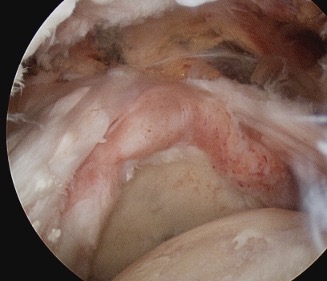

Tear patterns of supraspinatus and infraspinatus

| Crescent shaped | U shaped | L Shaped |

|---|---|---|

|

Small to medium tears Repair to footprint |

Large tears Need margin convergence then repair to footprint |

Antero-superior or postero-superior tears Need to mobilize cuff anterior or posterior |

Crescent, U shaped and massive rotator cuff tears